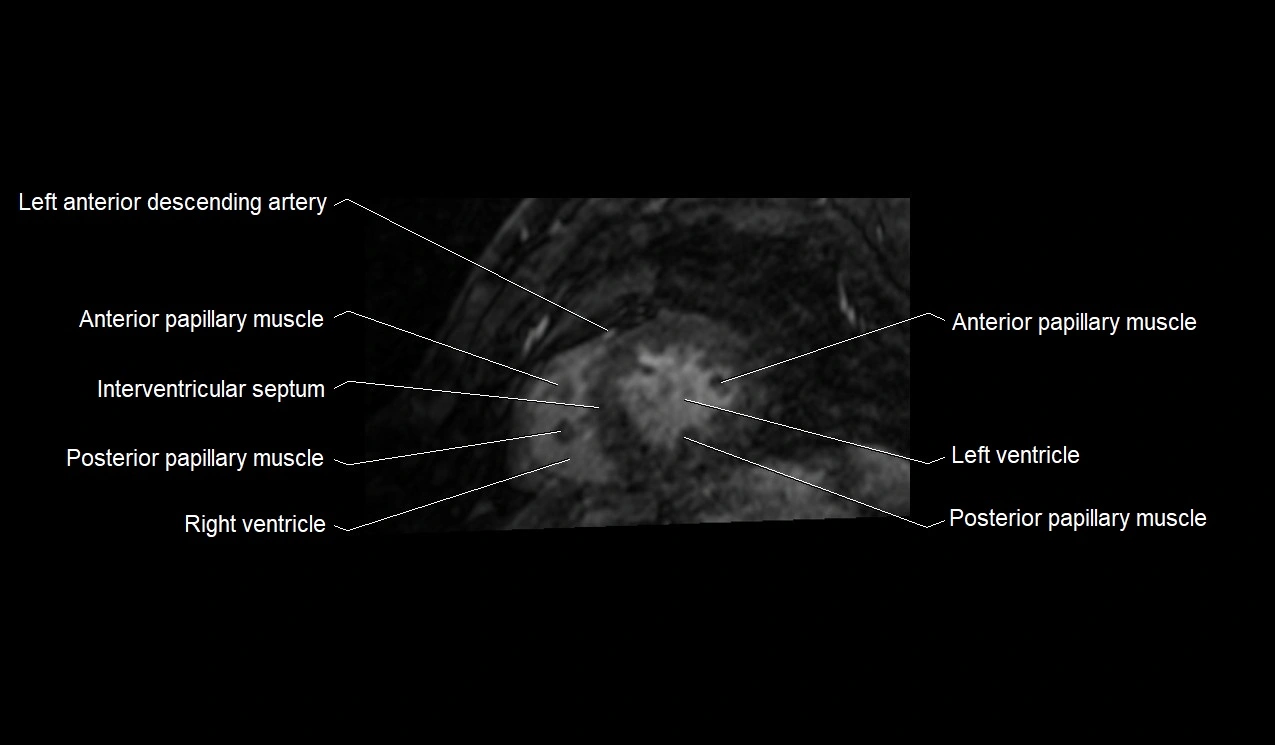

MRI image